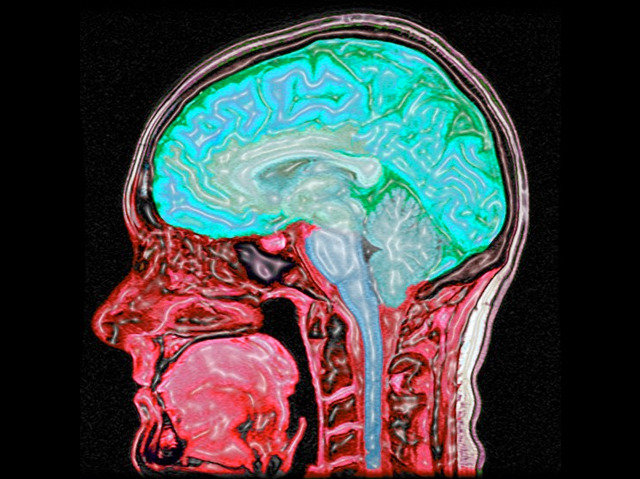

Brain Pain

Migraine affects 15 per cent of UK adults, leaving these individuals incapacitated by throbbing head pains, nausea and sensitivity to light. The cause is still unclear, though abnormal brain activity is thought to be involved, in particular overexcited pain pathways. Visualising human brain activity, using functional magnetic resonance imaging (a variant of conventional magnetic resonance imaging, pictured), demonstrates how migraine sufferers respond differently to pain. A brain region called the anterior cingulate cortex controls how we perceive pain. Activity in this region was higher in migraine patients than in healthy individuals, despite both groups being subjected to and perceiving the same level of pain. Migraine sufferers may acquire this different brain response to compensate for their overexcited pain pathways, bringing their pain perception down to that of healthy individuals. Understanding how a brain under the burden of migraine copes in painful circumstances may expose new targets for migraine treatment.